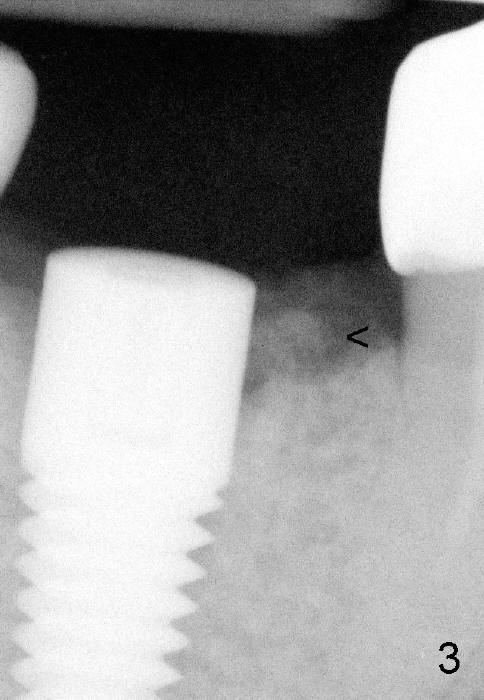

六十三岁台湾太太两年前右下第一磨牙准备做植牙,术前X光片显示缺牙区近中牙槽脊骨质好像有些特殊(图一箭头)。六乘十七毫米植牙(I)刚植入(图二,做了bone expansion),近中骨质好像又没有问题(箭头)。六个月后植牙近中骨质游离(图三箭头),除去骨片后,牙龈愈合,一个月后戴上牙冠(图四C),近中骨质仿佛没有异常。一年半后,病人突然回诊所,抱怨植牙周围流出臭味水,有些压痛。检查发现牙冠近中有个瘘道(图六箭头),下面好像有游离骨片,植牙牢靠,根尖片显示近中上部骨质稀疏(图五*),游离骨片(箭头)。翻开牙龈,除去相当大游离骨片,植牙粗糙面暴露(图七*,原有游离骨片所在地),除去炎性肉芽组织(+ +)后,植牙上部一两个螺纹暴露,箭头表示骨缺损边缘。反复用生理盐水冲洗,然后稀释四环素溶液冲洗,用探针和curet轻轻刮除植牙表面和螺纹菌斑,涂Straumann PrefGel,又用生理盐水冲洗,涂Endogain,植入Rocky Mountain Irradiated Allogenic Cancellous Bone and Marrow (图八*)。沐旭生医生认为植骨可能不管用,细菌很难清除,最好拔除植牙,植骨,然后再植牙。病人自己也意识到这个可能性,现在只有希望奇迹出现:缺损太大,不植骨身体可能无法修复。